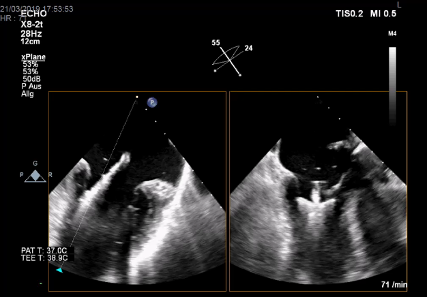

Im Oktober 2017 wurde in unserer OP-Gruppe der Hybrid-OP in Betrieb genommen. Dieser Herz-OP-Saal ist mit einer uniplanaren Fluoroskopie-Anlage, einem „high-end“ Echokardiographiegerät und hochauflösenden Monitoren ausgerüstet. Der Hybrid-OP wird von der Herzchirurgie, Kardiologie, Gefäßchirurgie und Interventionellen Radiologie genutzt.

Zur Steuerung der Interventionen werden Fluoroskopie, transösophageale Echokardiographie und Hämodynamik auf großen, hochauflösenden und für alle gut einsehbaren Monitoren wiedergegeben.

Während TAVIs in leichter Sedierung durchgeführt werden, benötigen andere Interventionen eine Allgemeinanästhesie: Transapikale oder trans-subclavia TAVI, transkatheter edge-to-edge repair der Mitral- und Trikuspidalklappe, transkatheter Mitralklappen- und Trikuspidalklappenersatz oder extra-anatomische bi-cavale Klappenimplantation (TricValve). Bei den herzchirurgischen transkatheter Eingriffen wird das Echo-Guidance von Mitarbeiter:innen unserer Abteilung bewerkstelligt.

Bildergalerie der Forschungsgruppe